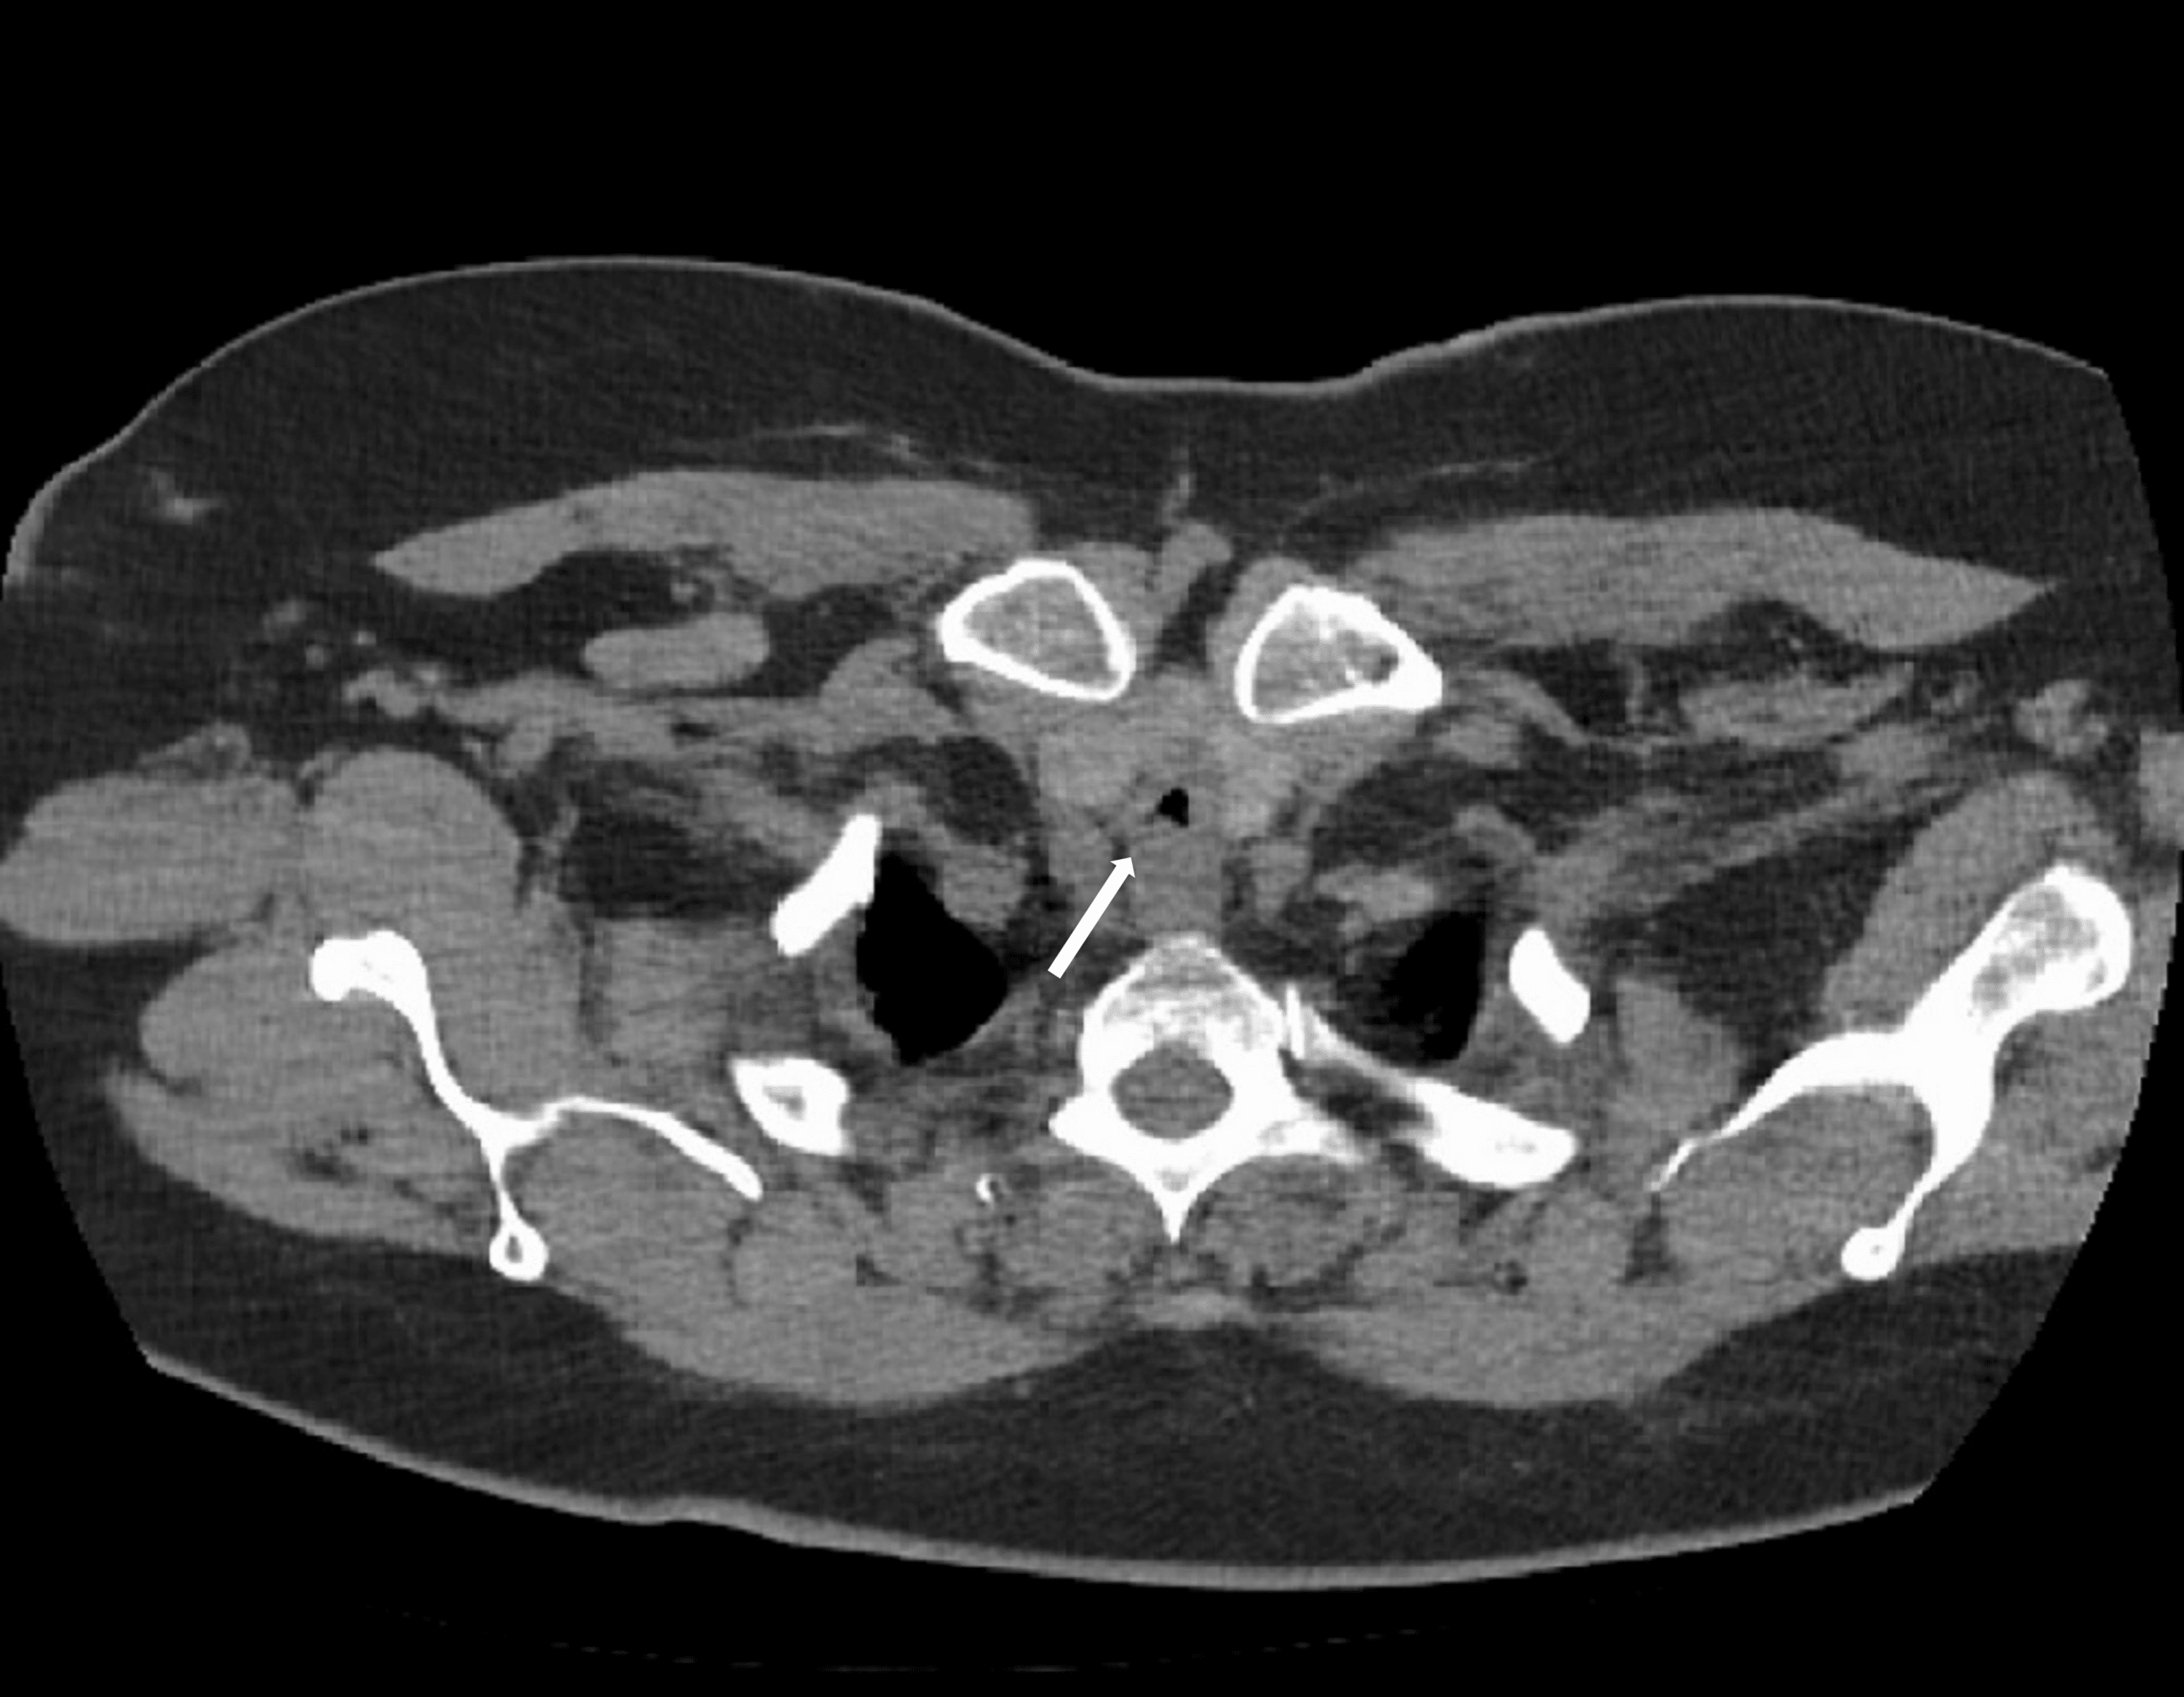

From www.cureus.com

Cureus AngiotensinConverting Enzyme InhibitorInduced Angioedema Tracheal Stenosis Following Endotracheal Intubation The most common procedure to correct postintubation tracheal stenosis was tracheal resection with an anastomosis between trachea. Nonmalignant tracheal stenosis is a potentially life threatening conditions that develops as fibrotic healing from intubation,. Although infraglottic stenosis most commonly results from endotracheal tube damage, it may occur after damage of the 1st tracheal ring or. Tracheal stenosis is usually acquired following. Tracheal Stenosis Following Endotracheal Intubation.